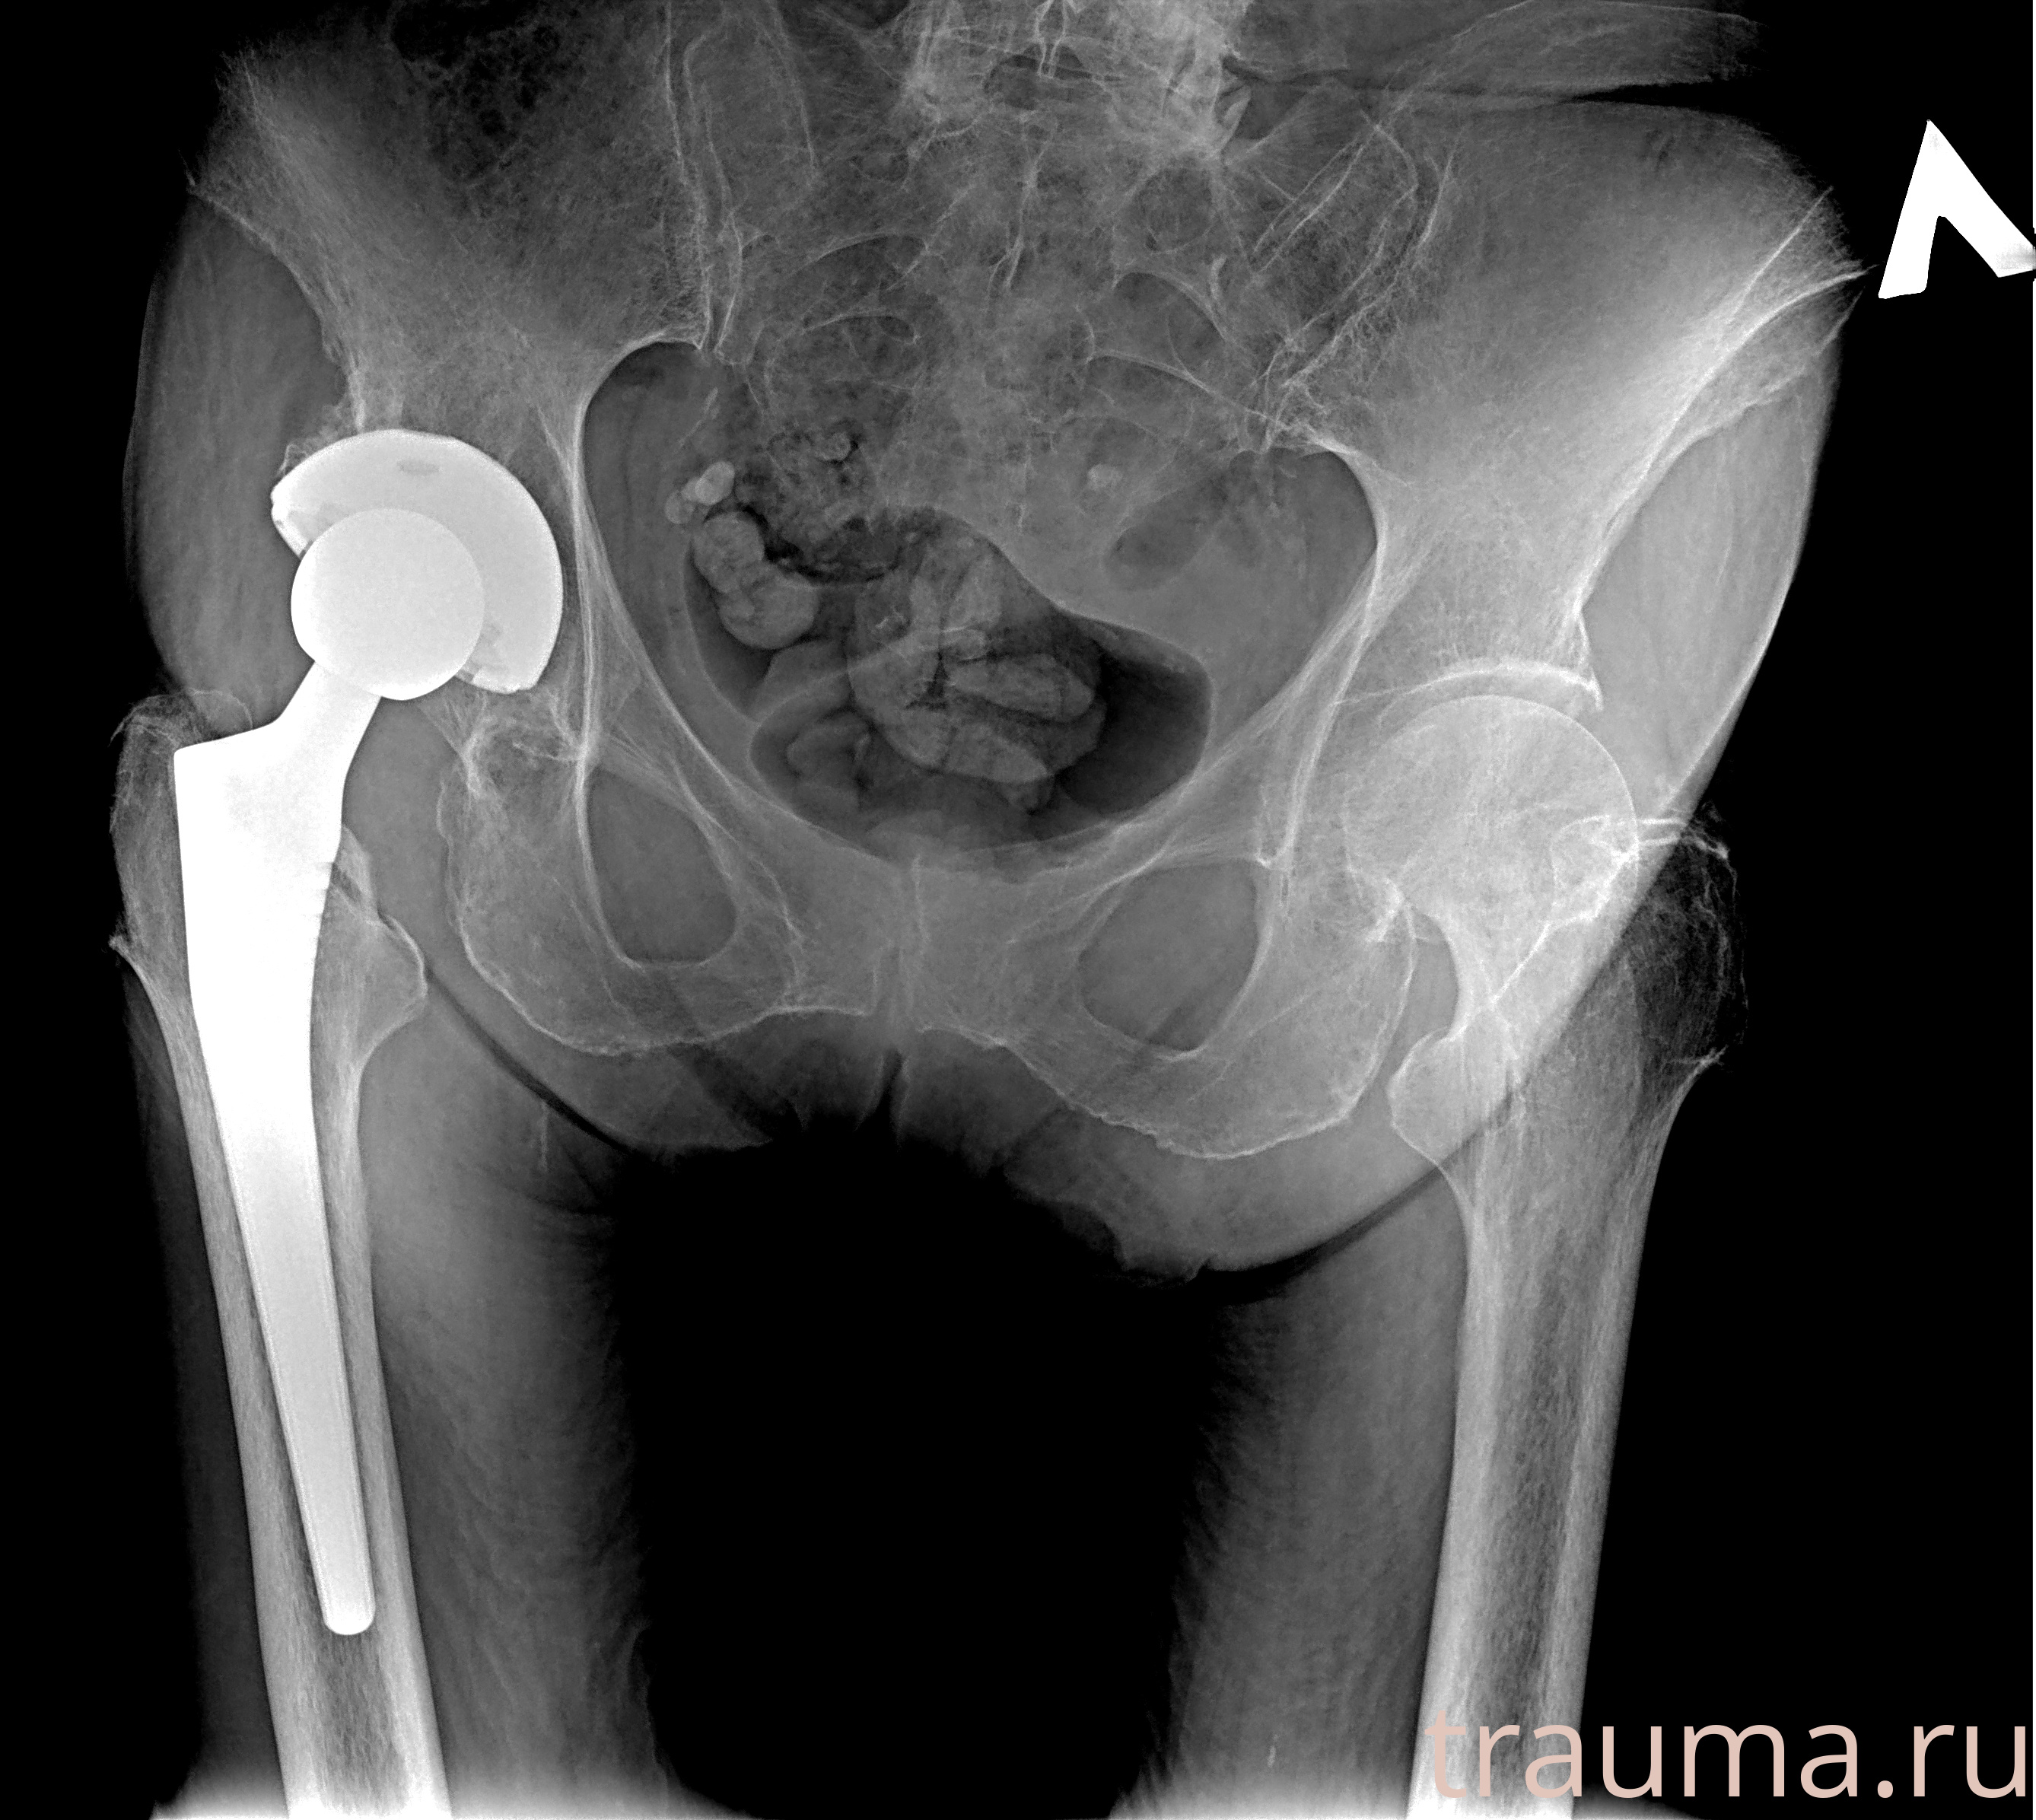

Первая помощь при переломе шейки бедра

Рентген на дому: по вашему адресу приезжает врач-рентгенолог, травматолог-ортопед с мобильным рентгеновским аппаратом, проводит диагностику травмы или заболевания, делает необходимые рентгенограммы, дает рекомендации по дальнейшему лечению. Получить качественные снимки в домашних условиях возможно благодаря уникальной методике, разработанной МосРентген Центром для института  Склифосовского